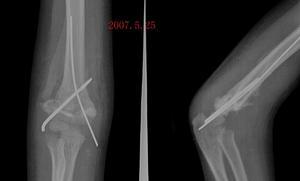

骨化性肌炎是指肌腱、韧带腱膜及骨骼肌的胶原性支持组织的异常骨化现象而言。骨外伤的一种并发症,又称创伤性骨化性肌炎。祖国医学属“骨折”范畴。分为两种类型,外伤性骨化性肌炎和进行性骨化性肌炎。其中以外伤性骨化性肌炎最常见。